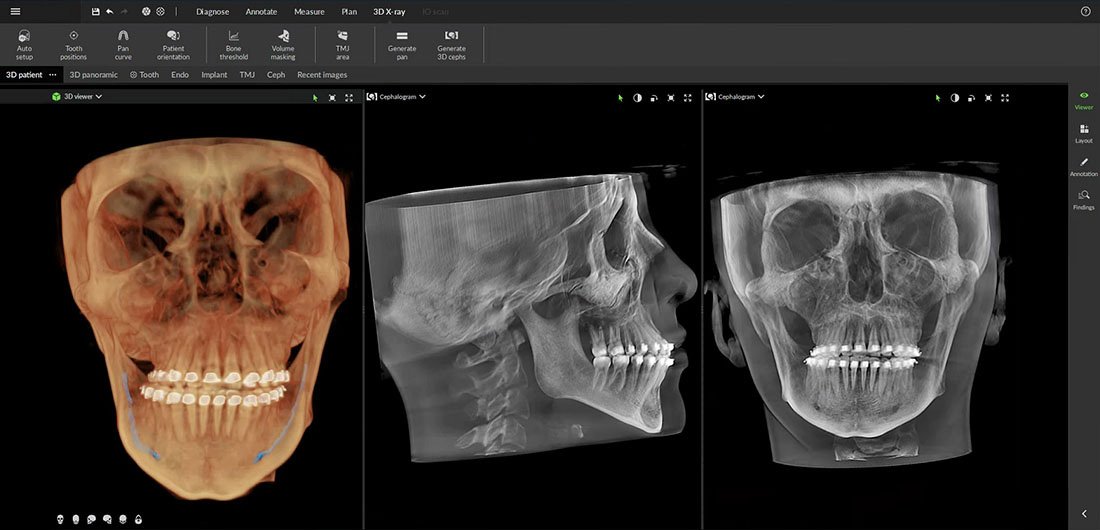

Cone Beam CT (CBCT) stands for cone beam computed tomography, a non-invasive imaging technique used in dentistry. During the procedure, the CT scanner emits a cone-shaped X-ray beam, capturing a series of two-dimensional images from various angles around the patient’s head. These images are then reconstructed to create a three-dimensional view of the oral and maxillofacial structures, including teeth, bone, nerves, and soft tissues. This comprehensive visualization allows for more accurate diagnosis and precise treatment planning.

Traditional panoramic X-rays can produce image distortions, making evaluation more challenging. In contrast, a dental CT scanner provides a proportionally accurate, distortion-free, three-dimensional image that can be viewed from multiple angles. It also reveals not only the quantity but also the quality of the bone. Additionally, CBCT exposes patients to lower radiation levels, as these devices do not emit radiation continuously like conventional dental CT scanners. Instead, CBCT operates with minimal radiation dose, ensuring a safer imaging process.

This advanced imaging technique allows for a true-to-scale (1:1) 3D representation of the examined area without superimposition, viewable from multiple angles. Additionally, it provides valuable information not only about bone quantity but also about bone quality.